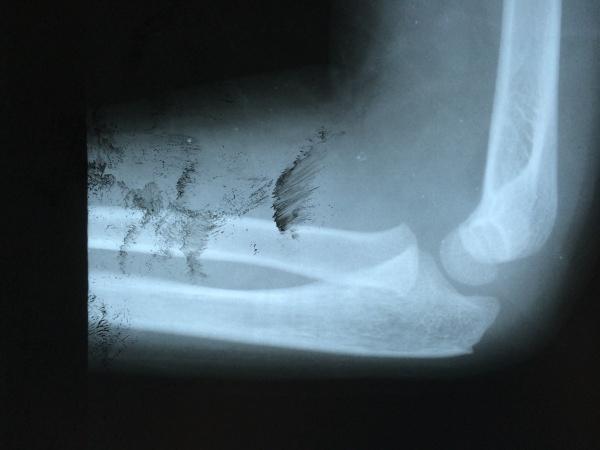

求高手看片并指导:是骨折片还是骨化中心?这两针打的道理何在?

是青少年阶段髌骨发育异常出现1个或多个副骨化中心,最常见于髌骨外侧

肘关节骨化